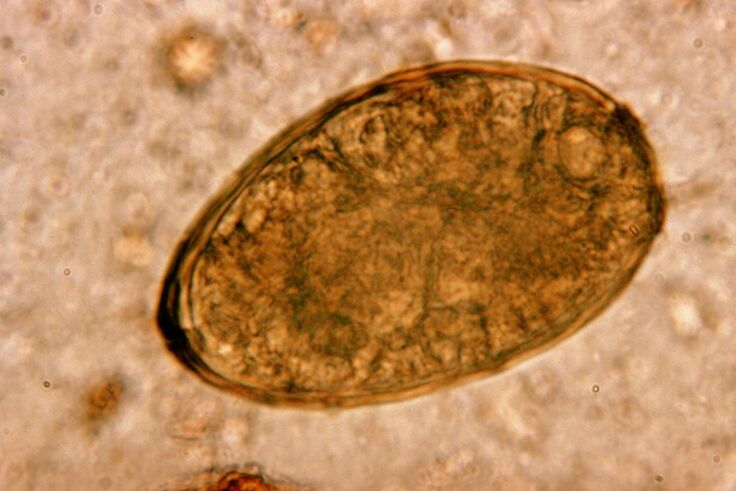

Дөңгелек құрттар, дөңгелек құрттар, жан-жақты және ішекте көбейеді. Олармен инфекция денеге тамақпен немесе жұқтырған адамның қолдары мен заттарынан кіретін жұмыртқалар арқылы пайда болады. Топырақ, жемістер, көкөністер, нашар пісірілген ет және балық - мұның бәрі гельминт жұмыртқаларын адам ағзасына енгізе алады.

Білу керек! Дөңгелек құрттар құрғақ жөтелді тудырады. Қан айналымы жүйесі арқылы көшу, олардың личинкалары тыныс алу мүшелеріне кіреді - бронх, трахея, өкпе - рецепторларды тітіркендіргіш және осы симптомға әкеледі. Личинкалардың бүкіл денеде көші-қон кезеңі - екі аптадан бір-екі апта.

Дөңгелек құрттар өте кең таралған, сондықтан аскариаз фонында жөтел - бұл әдеттегі құбылыс. Дөңгелек құрттармен инфекция гельминтия үшін дәстүрлі бағыттар арқылы жүреді. Оларға топырақпен байланыс, жуылмаған жемістер мен көкөністер мен лас қолдар жеу кіреді.

Ascaris личинкалары тыныс алу жүйесінің тіндеріне әсер ету арқылы проблеманы тудырады. Бұл паразиттің көші-қон кезеңі кезінде пайда болады. Адам тыныс алу жүйесіне айналма құрттардың әсер ету механизмі мен реттілігі келесідей.

Бір кездері асқазан-ішек жолында жұмыртқалар, жұмыртқалар, өз ферменттері мен ас қорыту шырынының әсерінен, личинкаларға бұрылып, қабығын төгіп тастады. Соңғысы ішек қабырғасынан қанға ену қабілетіне ие. Осыдан кейін олар бүкіл денеде қан алып жүреді - бауыр, жүрек, өкпе және тыныс алу жолына жету.

Трахеяның шырышты қабығында Силия бар, олар личинкаларды олардың рефлекстерімен жоғары тасымалдайды. Бұл жағдайда рецепторлар тітіркендіреді және жөтел пайда болады, гельминттерді аузына лақтырып, ішекке оралғаннан немесе жұтып, ішекке оралады.